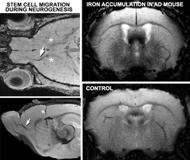

Metalloprotein-based MRI

We combine molecular engineering and MRI to modulate contrast in brain cells via the expression of novel iron-binding, paramagnetic metalloproteins in the ferritin family. Following transgene expression, the ferritin shells sequester physiologically available iron, and biomineralization of the ferritin core renders the complex paramagnetic, producing MRI contrast. By combining an MRI reporter with a cellspecific expression, a multitude of applications exist. For example, we can track cell migration after neurogenesis. More recently, we have employed the same MRI approaches optimized for iron imaging to evaluate iron accumulation in models of Alzheimer’s disease.